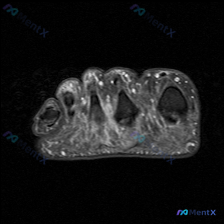

足部MRI见软组织弥漫高信号,别只想到蜂窝织炎!

给大家分享一份足部MRI读片病例,整理了完整的分析思路,一起来讨论一下。

这是一份足部前足区域(跖骨头/趾骨近端水平)的横断面MRI T2序列图像,核心观察结果如下:

- 骨骼:中央跖骨头/趾骨骨皮质呈低信号,骨髓腔信号正常

- 软组织:骨骼周围可见广泛不均匀信号异常,T2序列呈弥漫性高信号

- 解剖间隙:原本的跖骨间隙、趾间软组织脂肪信号被弥漫高信号取代,提示液体积聚/水肿

- 病变特点:弥漫性分布,无明确单一局限性肿块,边界模糊,呈浸润性延伸,无明显典型占位推压效应